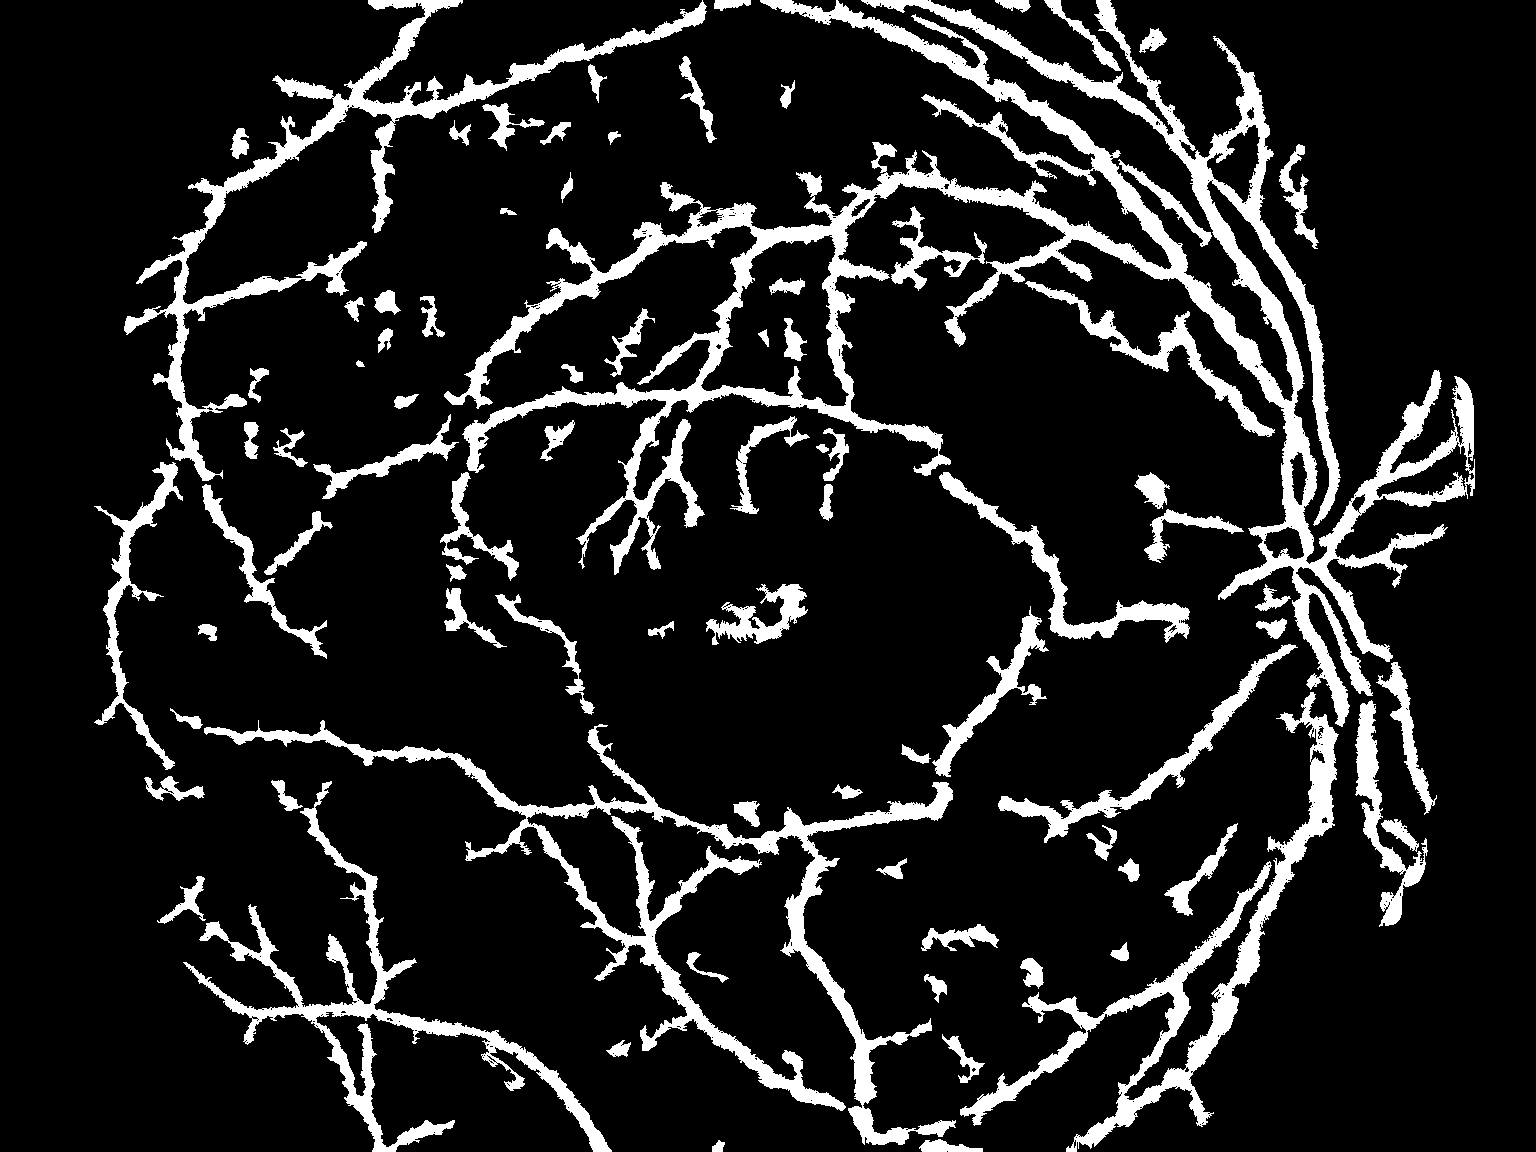

低阈值图像

Hi阈值图像

筹备和清理:

current = np.copy(thresh_hi)

prev = np.copy(current)

prev[:] = 0

current = cv2.morphologyEx(current, cv2.MORPH_OPEN, kernel5)

iter_num = 0

max_iter = 1000不是最有效的方法.但易于实施:

while np.sum(current - prev) > 0 and iter_num < max_iter:

iter_num = iter_num+1

current = cv2.dilate(current, kernel3)

current[np.where(thresh_lo == 0)] = 0

初始掩模

去除小气泡:

contours, hierarchy = cv2.findContours(current, cv2.RETR_LIST, cv2.CHAIN_APPROX_SIMPLE)

for contour in contours:

area = cv2.contourArea(contour)

if area < 256:

cv2.drawContours( current, [contour], 0, [0,0,0], -1 )

去除小气泡后

形态清理:

opening = cv2.morphologyEx(current, cv2.MORPH_OPEN, kernel7)

cl1[np.where(opening == 0)] = 0

结果

这绝不是最优的,但我认为它应该为您提供足够的启动工具。